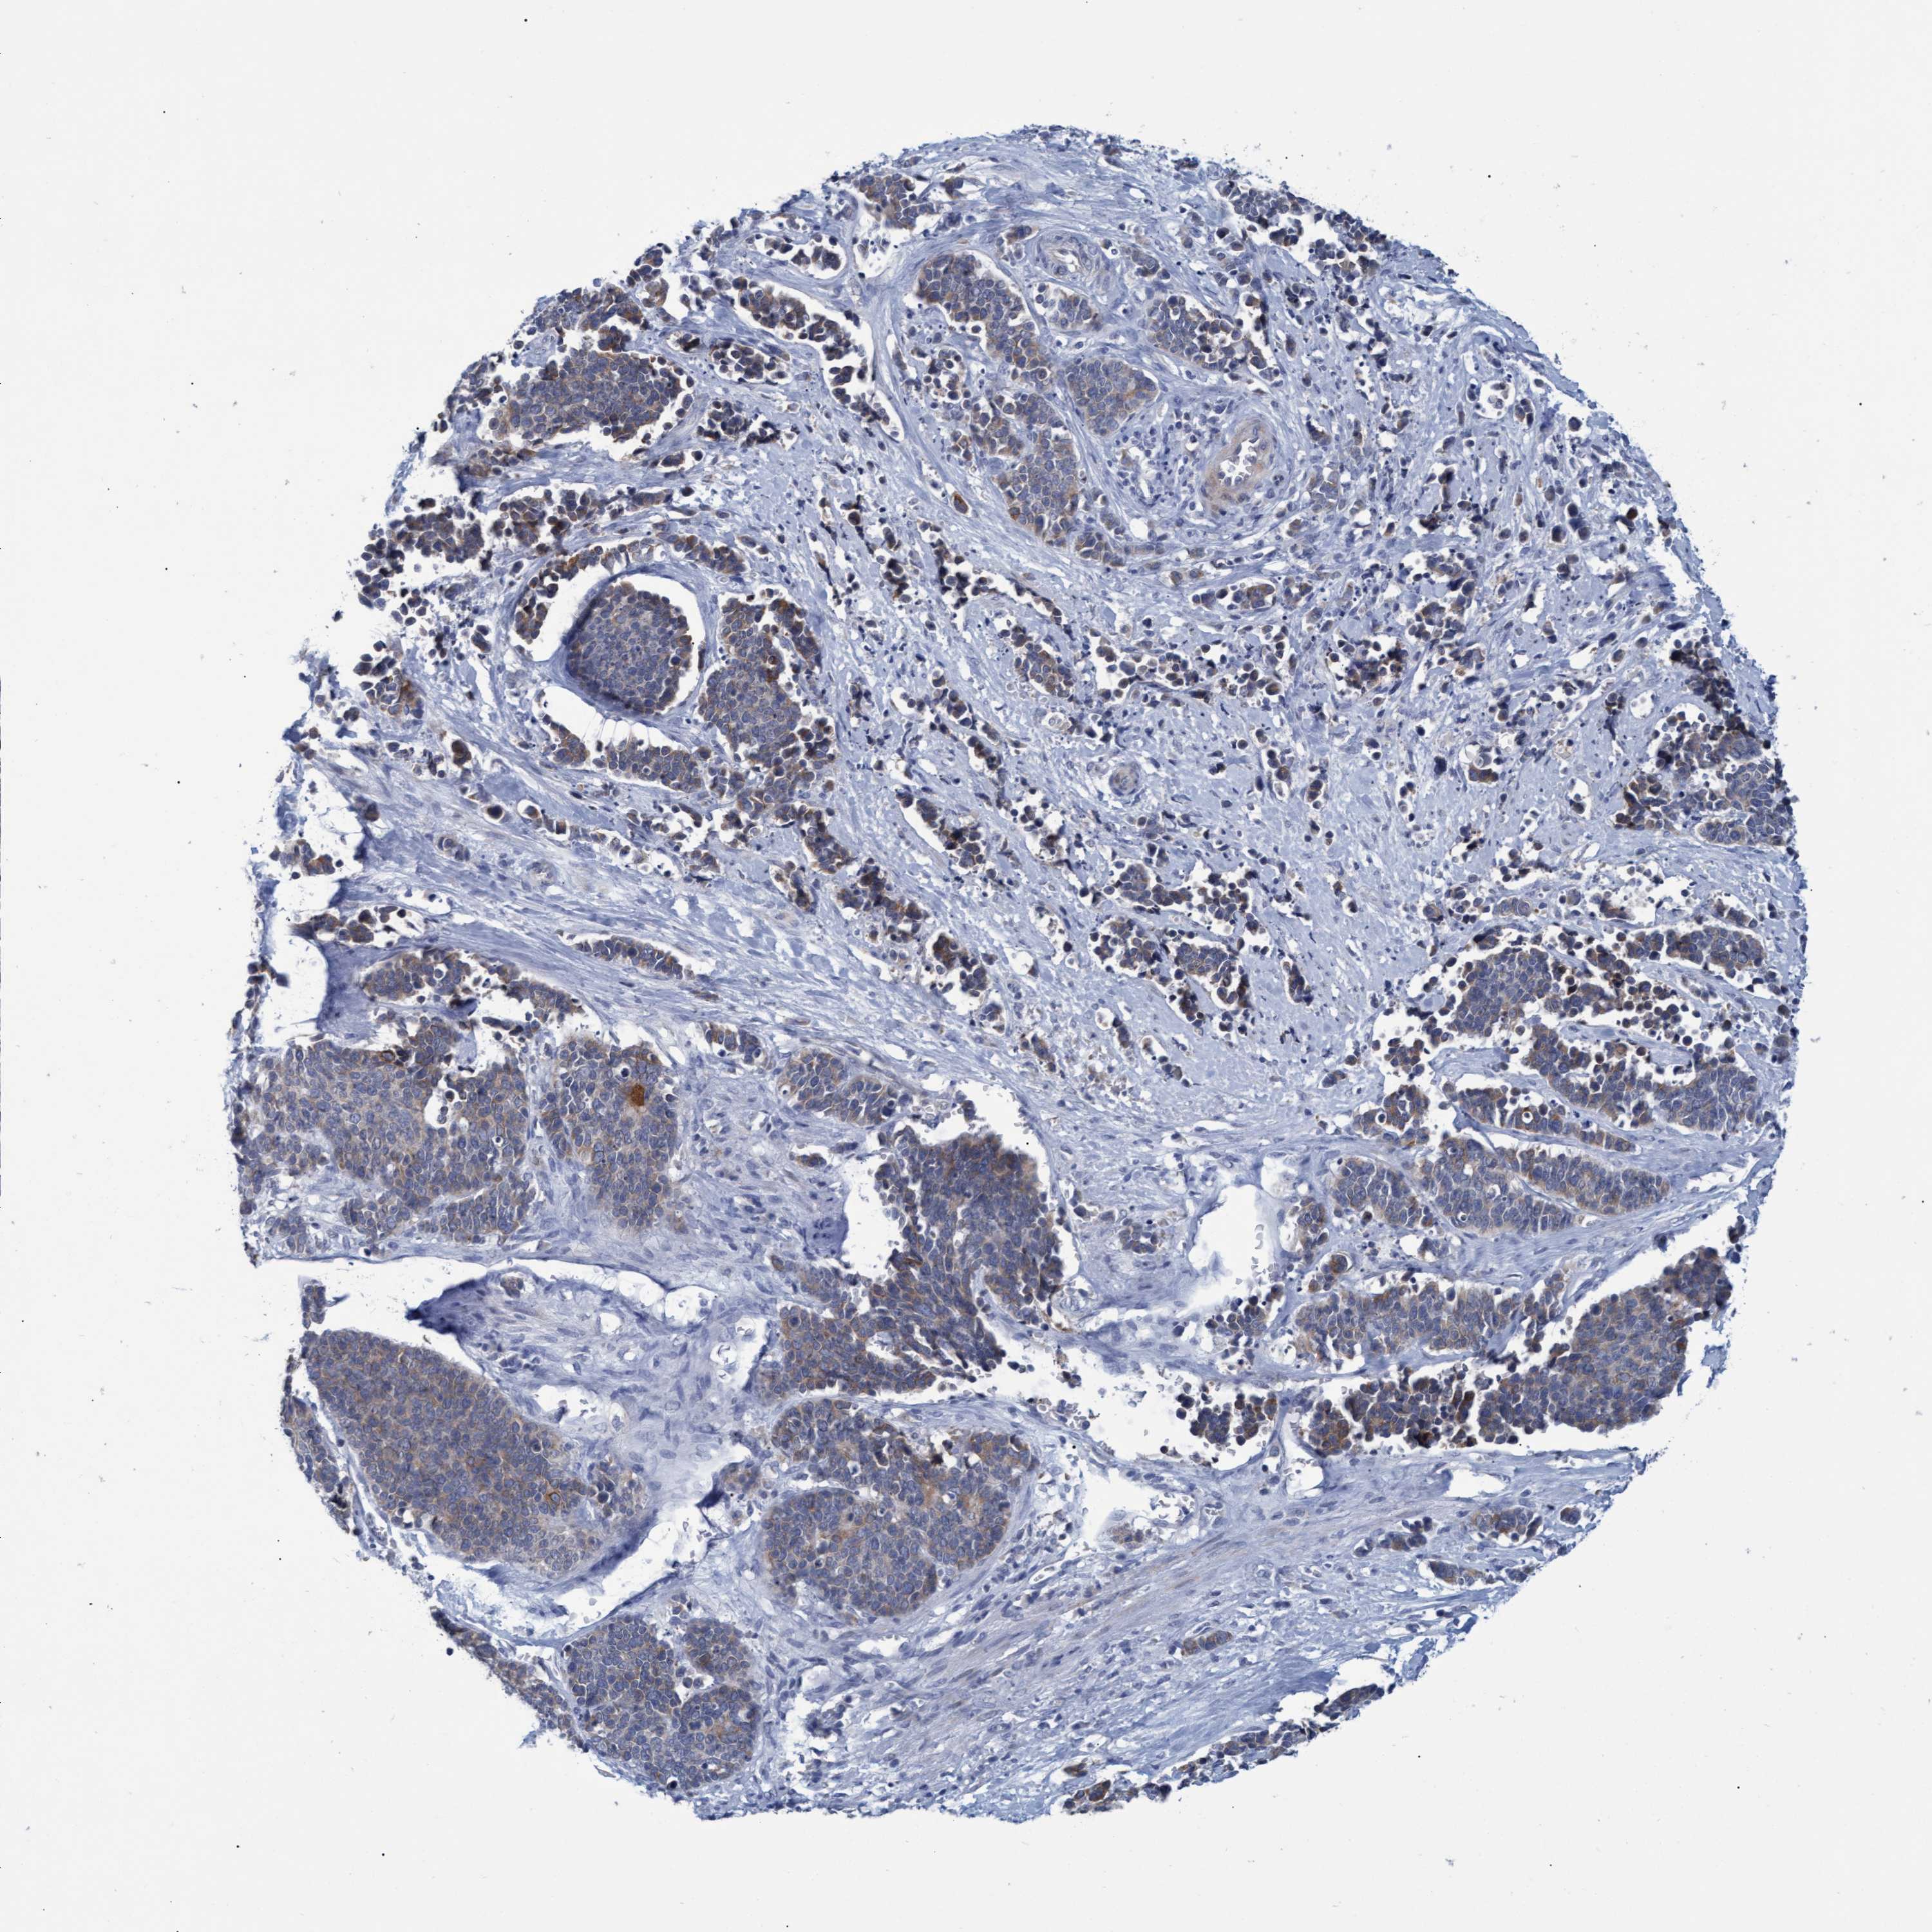

CERVICAL CANCER - Protein expressioni

A mouse-over function shows sample information and annotation data. Click on an image to view it in a full screen mode. Samples can be filtered based on level of antibody staining by selecting one or several of the following categories: high, medium, low and not detected. The assay and annotation is described here.

Note that samples used for immunohistochemistry by the Human Protein Atlas do not correspond to samples in the TCGA dataset.

Antibody stainingi

Antibody staining in the annotated cell types in the current human tissue is reported as not detected, low, medium, or high, based on conventional immunohistochemistry profiling in selected tissues. This score is based on the combination of the staining intensity and fraction of stained cells.

Each image is clickable and will lead to virtual microscopy that enables deeper exploration of all samples and also displays staining intensity scores, fraction scores and subcellular localization as well as patient and tissue information for each sample.

Antibody CAB022647

Staining

High

Medium

Low

Not detected

Intensity

Strong

Moderate

Weak

Negative

Quantity

>75%

75%-25%

<25%

None

Location

Nuclear

Cytoplasmic/membranous

Cytoplasmic/membranous,nuclear

Squamous cell carcinoma, NOS

Adenocarcinoma, NOS